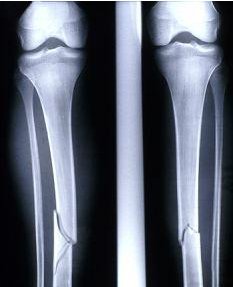

腿部骨折通常是由于交通事故或体育运动导致